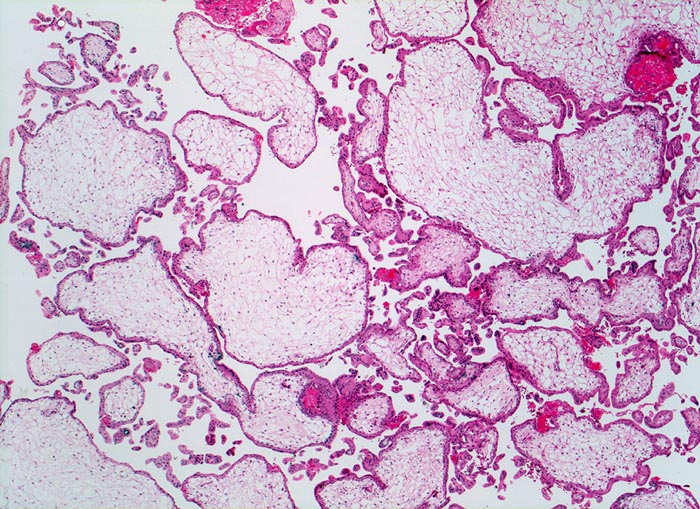

PathoPic – image database / PathoPic ID 3725 - Partialmole bei Triploidie

Partialmole bei Triploidie

Grosse plumpe mangelhaft verzweigte Zotten. Mangelhafte Vaskularisation und hydropische Umwandlung des Stromas der Plazentarzotten.

Karyotyp 69, XXX

Im Gegensatz zur Mole nur geringe Trophoblastproliferation. Bei Partialmolen liegt ein diploider Chromosomensatz des Vaters und ein haploider der Mutter vor. Triploidien lassen sich bei etwa 15% chromosomal bedingter Aborte nachweisen. Triploide Früchte erreichen nur extrem selten Geburtsreife.